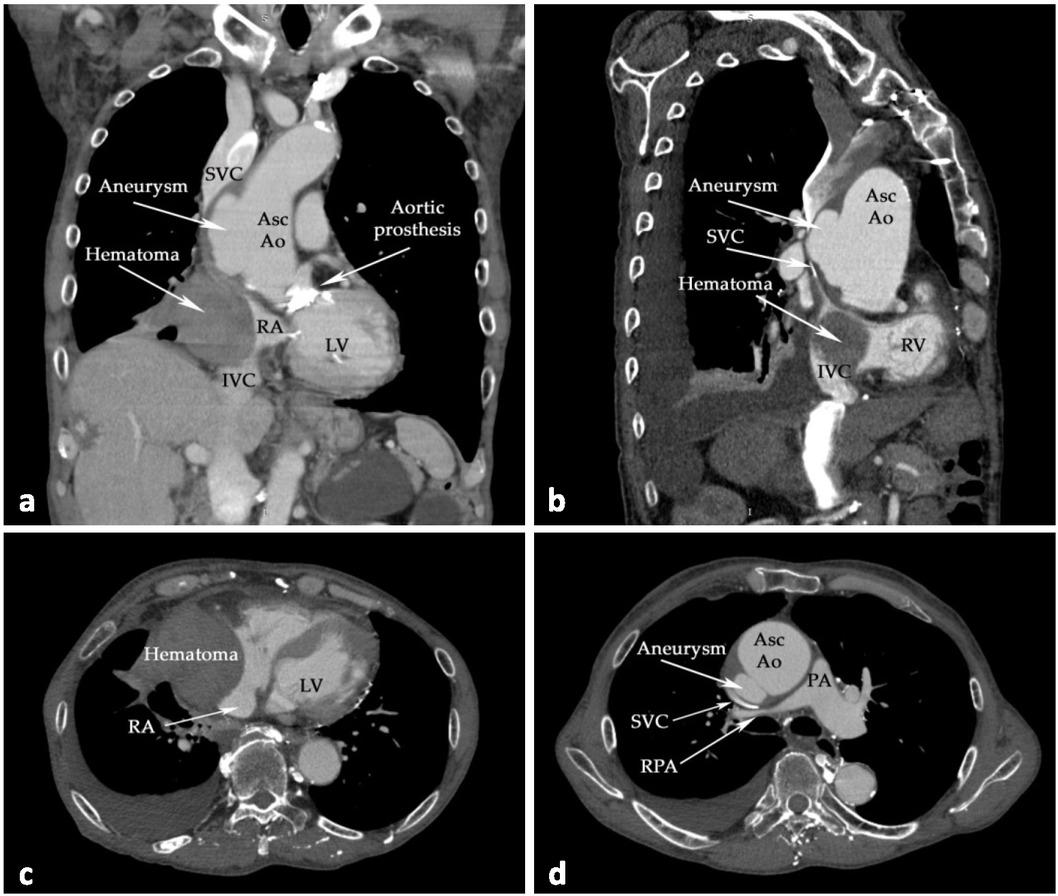

Fig. 2